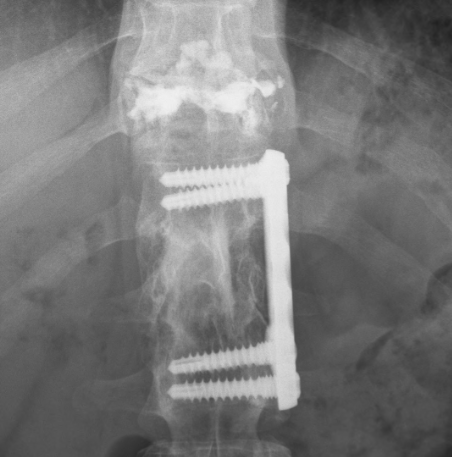

It’s been about a month since the doctors were able to perform a pretty miraculous procedure on my back. The accident burst my T11 vertebrae and since I already have a fusion and plates from T12-L2 the initial diagnosis was that to keep the spine supported they were going to have to fuse from T9 or T10 all the way down to L3 or L4 with the addition of rods/plates going from top to bottom of those locations. I told Dr. Sipos that I would prefer not to have such an invasive surgery and if he had any other options, initially he said that there was to much damage and that this was going to be the most feasible option, so I asked him to take a day or so and see if he could come up with any other options. He came to me the next day and said he had one other option of (for lack of better terminology) cementing the T11 vertebrae, removing all the extra bone fragments, and grinding down the portions that were pressuring the spine. It was not certain that it would work because of the amount of current injury and past injury, so he asked if I would like to take that option but if when he was performing the surgery he was not able to complete that option he had my permission to go with the full fusion from top to bottom as explained above. Of course I agreed and hoped for the best.

Needless to say his amazing talent worked out and he was able to perform the rebuilding of that vertebrae without having to insert and extra metal or fusions. Here are some pictures of what he was able to do and my current back.